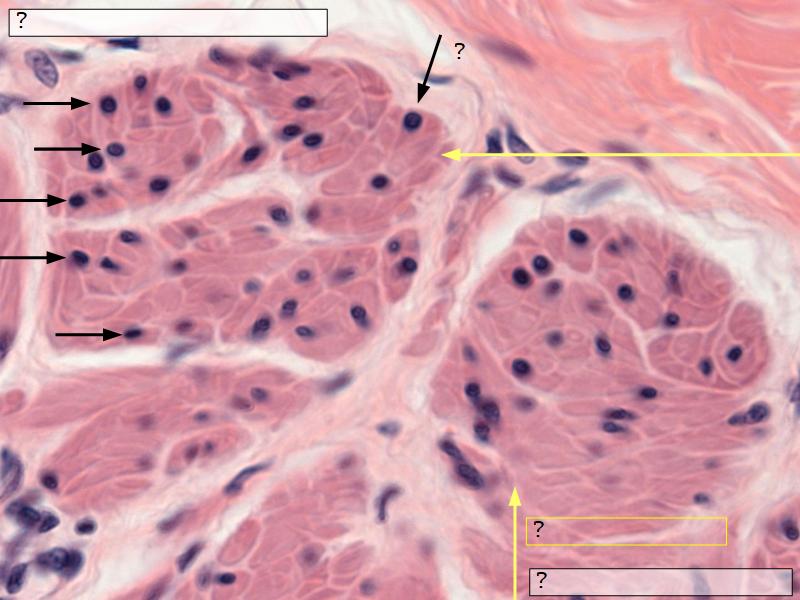

- Interlaced with smooth muscle fibres

- Smooth muscle

- Fibres and bundles